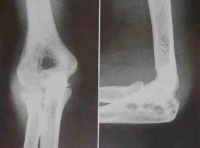

(6)X线摄片显示肘关节有骨破坏,关节间隙狭窄或消失。

X线摄片单纯滑膜结核显示局部骨质疏松和软组织肿胀。在鹰嘴或外踝中心型结核,可见死骨形成。若病变累及邻近骨干,可见骨膜性新骨形成。早期全关节结核,可见关节边缘局限性骨质破坏,或轻度关节软骨骨板模糊。晚期全关节结核,关节软骨下骨板广泛模糊,关节间隙变窄。窦道继发感染骨质显示硬化。